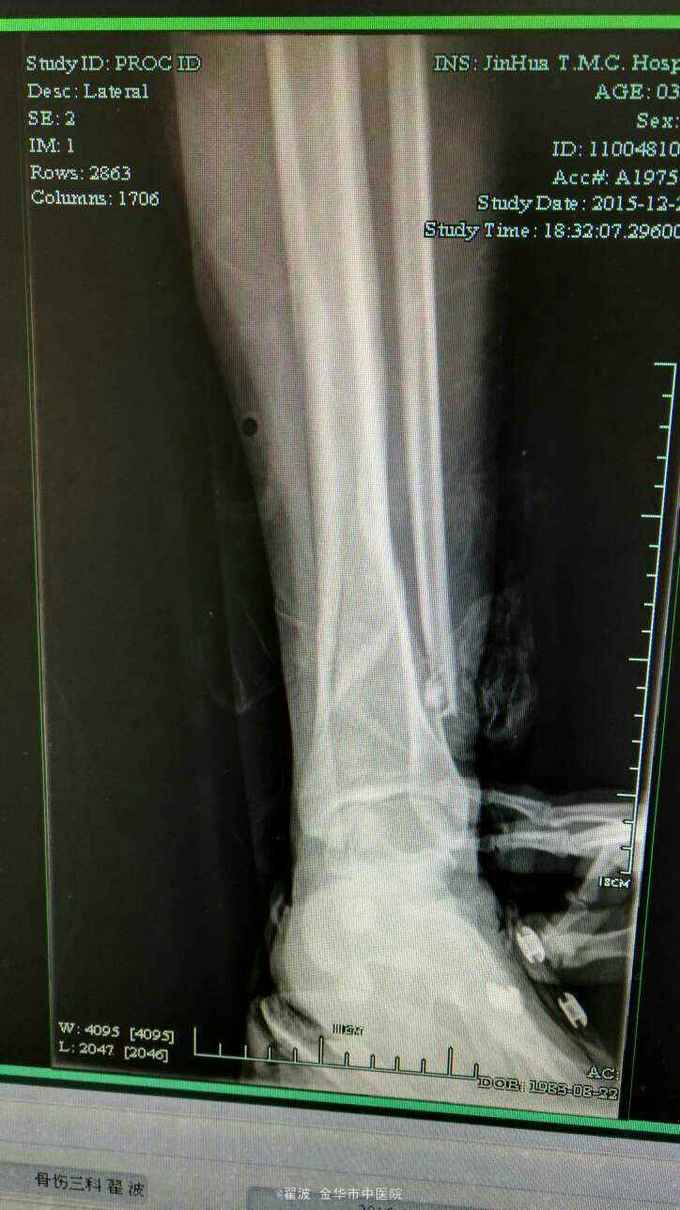

主诉:高处坠落致右小腿肿痛活动受限2小时 病史:患者2小时前从2米高处摔下,致右小腿疼痛,局部肿胀,活动受限。由家人送至我院急诊就医,摄片提示右胫腓骨粉碎性骨折,遂收住入院,入院后予抬高患肢,石膏固定,冰敷。

查体:右小腿下段肿胀明显,皮肤无破损,压痛阳性,可及骨擦感,并有异常活动,右下肢轴向叩击痛阳性,肢端感觉及血运正常,踝关节活动受限。